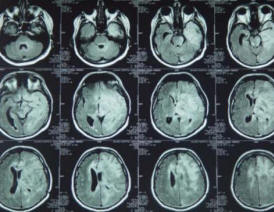

19-AUGUST-2008  AHMAD FAYSAL OEDEH  38 YEARS  MALIGNANT HIGH GRADE ASTROCYTOMA LEFT TEMPORO-FRONTAL LOBES WITH IMPENDING CONNING.

CT-scan of the brain done 11-August-2008 showed left fronto-temporal mass. MRI done 12-August-2008 confirming the presence of wide-spread mass infiltrating the left fronto-temporal lobes with shifting of the midline structures and pending conning. High-grade astrocytoma was in the top of the diagnosis and glioblastoma multiforme could be the second in the list.

MRI  03-June-2010 before Avastin and CAMPTO MRI 01-July-2010 after 2 courses